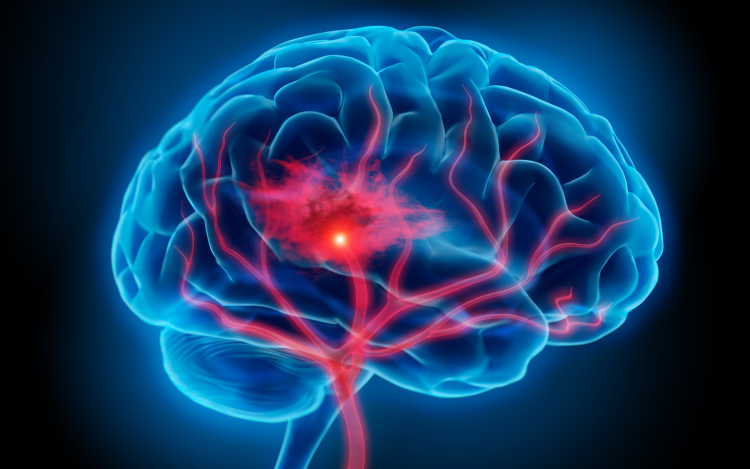

Óránként egy halálesetért a stroke felelős

Magyarországon évente 45 ezren kerülnek kórházba stroke miatt, óránként egy halálesetért felelős a betegség - mondta Bereczki Dániel, a Magyar Stroke Társaság elnöke az M1 aktuális csatornán szombat este.

Hozzátette, ma már tízezer alatt van azoknak a száma, akik belehalnak a stroke-ba, ami jelentős csökkenés 1980-hoz képest, amikor évente mintegy 24 ezren haltak meg ebben a betegségben.

Mint mondta, ennek oka, hogy az emberek egyre komolyabban veszik a kockázati tényezőket, elsősorban a magas vérnyomást, cukorbetegséget, a szívritmuszavart, és a magatartásbeli tényezők között a dohányzást.

Nem csak az idősebbek vannak kitéve a stroke veszélyének, Magyarországon az esetek több mint 10 százaléka 50 éves kor alatt, több mint 27 százaléka munkaképes korban jelentkezik - mutatott rá.

Kitért arra, hogy a stroke három fő tünete, amikor azonnal mentőt kell hívni, mert 3 óra van az eredményes beavatkozásra, az egyik oldali végtag meggyengülése, a száj félrehúzódása és a beszéd elakadása.

A szakértő elmondta, a betegek csak 5 százaléka kapta meg a vérrögoldó kezelést tavaly, mert későn mentek kórházba. Az európai átlag 10 százalék, tehát vannak még feladatok - jegyezte meg.